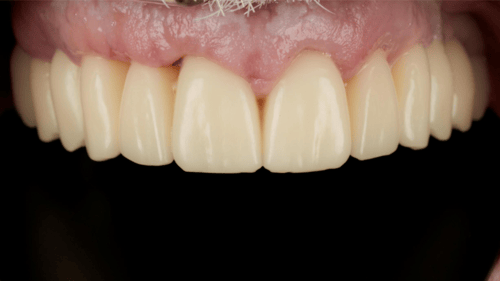

Implant positions were indexed to the archived diagnostic design, enabling a same-day, digitally fabricated conversion prosthesis requiring no luting or bite adjustment. The provisional functioned as both a healing appliance and a prototype for the final restoration.

Implant match Digital conversion prosthesis

By eliminating analog impressions, physical models, and chairside conversions, this EZ Load workflow reduced surgical time and compressed treatment to as few as two predictable clinical appointments. The digitally archived data also enables rapid reproduction of the provisional or final prosthesis, improving efficiency and long-term predictability